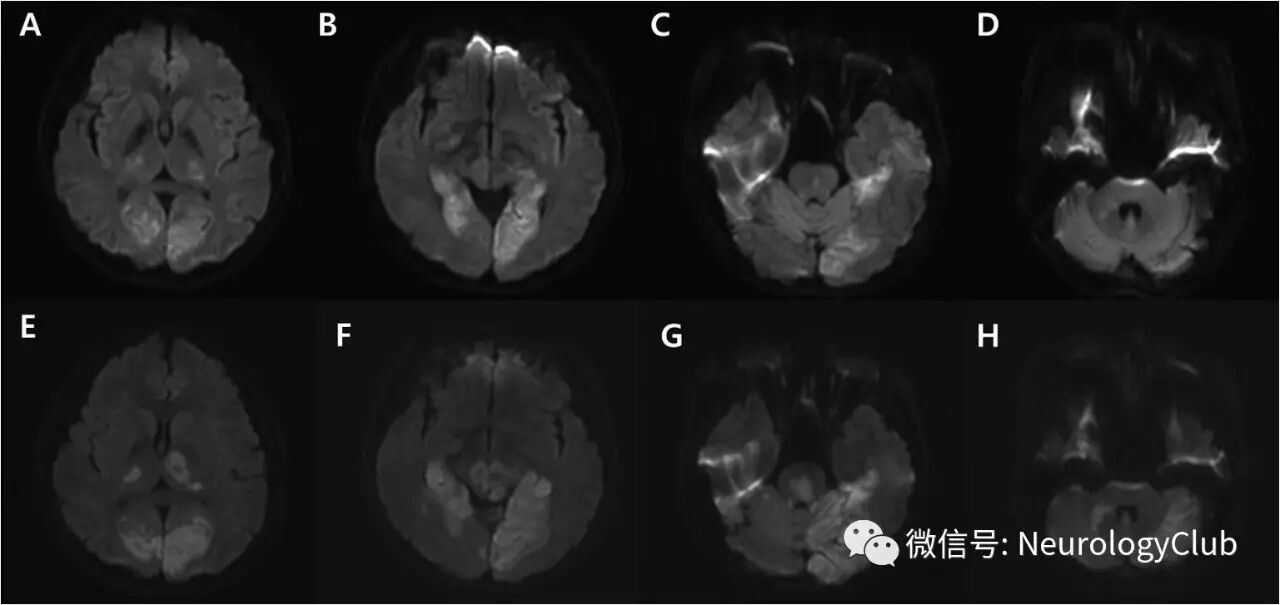

1天后复查DWI,见病灶延伸累及双侧丘脑后部,中脑,脑桥和小脑(图1E-H)。T2WI可见颞枕叶血管源性水肿,梯度回波序列上左侧丘脑,左侧枕叶,中脑,脑桥和左侧小脑(图2A-B)点状出血。此外,梯度回波序列还可见沿着左侧枕叶脑沟的晕状伪影(blooming artifact),符合皮层静脉血栓形成(图2B,箭)。MRA同样未见颅内动脉狭窄或闭塞(图3A)。后一天再复查梯度回波序列可见点状出血进展,MRV上直窦管腔不规整(图3B,箭)。

(图1:A-D:起病初DWI;E-H:复查DWI)

(图2:A:T2WI可见血管源性水肿;B:梯度回波序列可见点状出血和晕状伪影[箭];C-D:梯度回波序列证实点状出血进展